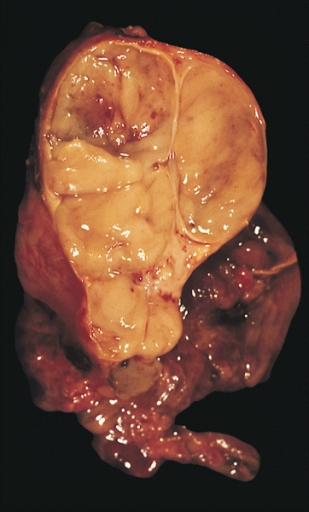

Thymectomy

This is su rgical removal of the thymus gland.

It is usually performed on patients with a tumor of the thymus (thymoma) and patients younger than age 55 with generalized MG.

Benefits of thymectomy develop gradually and most improvement occurs years after the procedure is performed.

Image Courtesy of

https://commons.wikimedia.org/wiki/File:Encapsulated_thymoma.jpg

This image is in the public domain and thus free of any copyright restrictions.